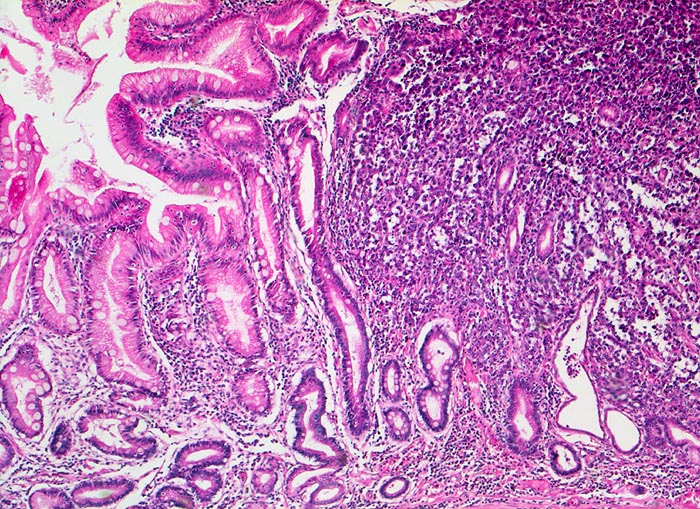

Morphologische Merkmale:

• Am unteren Ende des Präparates Antrummukosa mit mässiggradiger chronischer, geringgradig aktiver Gastritis und ausgedehnter intestinaler Metaplasie (Becherzellen).

• Weiter oben Invasion der Magenschleimhaut durch ein teils solides, teils drüsenbildendes Adenokarzinom mit stark atypischen Tumorzellen.

• Fokale Erosion des Karzinoms bedeckt von fibrinoleukozytärer Membran.

• Tumorinfiltration der Submukosa an der oberen Präparathälfte.

• Der invasive Karzinomanteil zeigt teilweise muzinöse Differenzierung (teils siegelringzellige Tumorzellen schwimmen in extrazellulären Schleimseen).

• Tumorfreie Lamina muscularis propria.